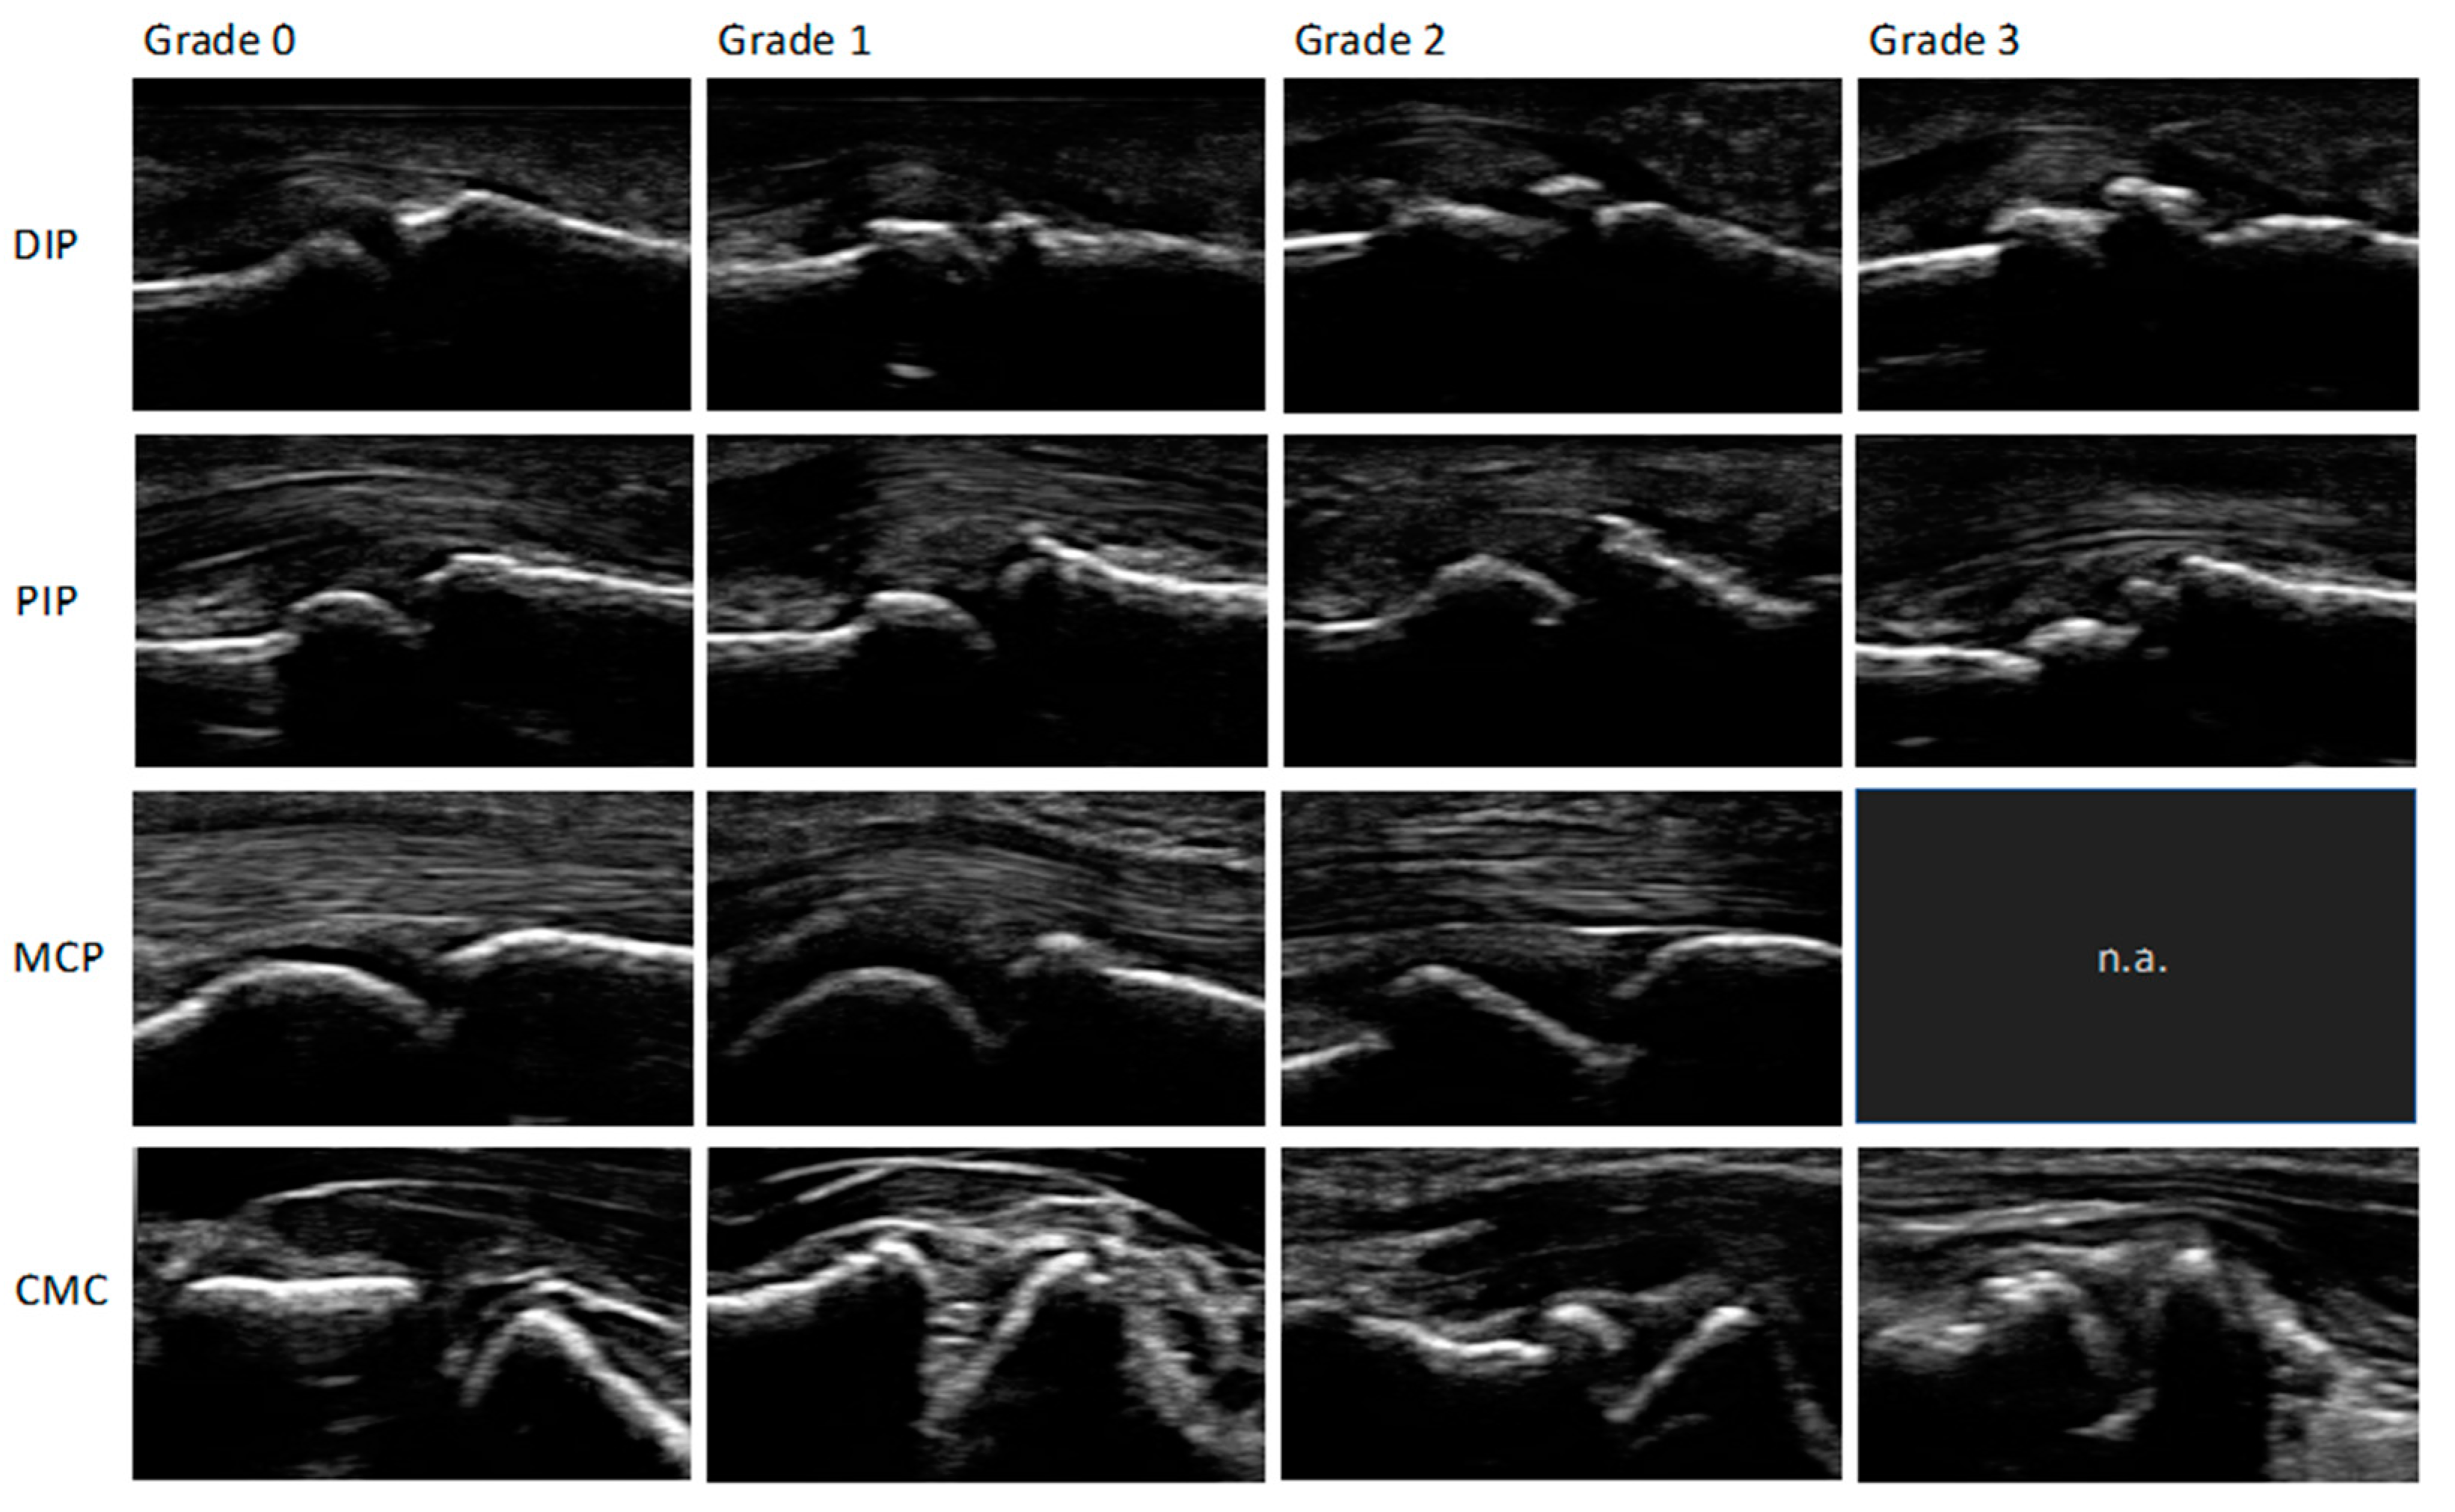

To read the images, a modified (palmar, not dorsal view) semi-quantitative score for osteophytes ranging from 0-3: 0 = no osteophytes, 1 = mild osteophytes, 2 = moderate osteophytes and 3 = severe osteophytes was used. An increase in the score describes an increase in the severity of the osteophytes found. The biggest osteophyte at each joint was scored. The score was previously described by Keen et al., Kortekaas et al., Mathiessen et al. and was evaluated and recommended by the Outcome measures in Rheumatology ultrasonography (OMERACT) group [9,10,11,12,13]. If one or more joints of the participant showed osteophyte values ≥1, they were positively defined of showing HOA signs. The pictures were scored by a medical student (MG) in a consensus read with an experienced rheumatology resident (PS). Figure 1 shows a normal MCP joint without any major pathologies. Figure 2 shows an example of the different grades of osteophytes for each joint group in palmar view.

At least one grade 1 osteophyte was found in 426/427 participants (99.8%). Grade 1 osteophytes were present in 184 (43.0%), Grade 2 in 240 (56.2%), and Grade 3 in 22 (5.2%) participants (Figure 3). No grade 3 osteophyte was found at any MCP joint.

Figure 2. Osteophytes Atlas: Figure 2 shows an example of the different grades of osteophytes (0-3) for each joint group (DIP = distal interphalangeal joint; PIP = proximal interphalangeal joint; MCP = metacarpophalangeal joint; CMC = carpometacarpal joint in palmar view.) No grade 3 osteophyte was found at any MCP joint.